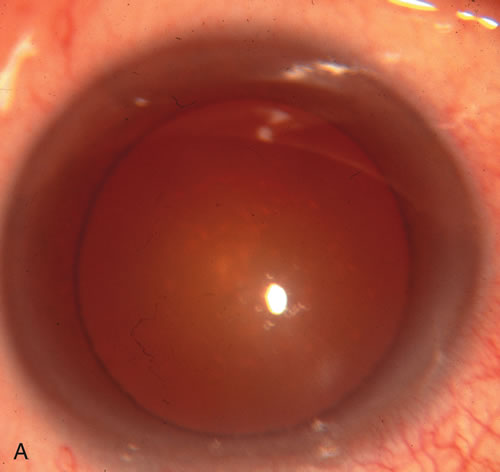

Cataract extraction by any technique performed in a patient with a pre-existing filter will have an effect on the previous filtering bleb.121–124 Bleb failure is more likely with ECCE compared with small-incision phacoemulsification.125 However, even patients undergoing topical anesthesia with clear corneal phacoemulsification and foldable IOL may experience bleb failure. One of three patients with a functioning filter and preoperative mean IOP of 12 mm Hg without antiglaucoma medications experiences bleb failure after lens extraction (Table 2). These patients require long-term drug therapy or bleb needling to control IOP. 126 Additional incisional glaucoma surgery may eventually be required in up to 10% of patients.127 Intraoperative iris manipulation may cause significant breakdown of the blood–aqueous barrier, resulting in inflammation that causes bleb failure. Even after uncomplicated clear corneal phacoemulsification, IOP may increase an average of 2 to 3 mm Hg due to bleb fibrosis.128 Approximately 20% of filtered patients require a long-term increase in glaucoma medications following uncomplicated clear corneal phacoemulsification with a foldable copolymer acrylic IOL129 (Fig. 3). In situations in which the bleb is not working at all, the eye will have a postoperative pressure spike that mimics that in the patient not having had a prior filtering procedure. In situations in which the bleb is marginal, the pressure spikes tend to be lower, and the final postoperative IOP tends to be around 50% higher than it was preoperatively. These patients require combined procedures in order to reestablish long-term filtration. In situations in which the bleb is very thin, polycystic, and associated with an IOP around 5 to 8 mm Hg on no antiglaucoma therapy; uncomplicated cataract extraction will have a minimal effect on the level of IOP. Patients with functioning glaucoma drainage implants usually have minimal long-term changes in IOP after uncomplicated cataract extraction.130

Fig. 3. Partial bleb failure following clear corneal phacoemulsification with foldable IOL. A. Preoperative bleb appearance prior to temporal lens extraction. Preoperative IOP was 12 mm Hg on no antiglaucoma medications. Time from 5-FU trabeculectomy surgery to lens extraction was one year. B. Bleb appearance 2 months after clear corneal cataract surgery with topical anesthesia. Following lens extraction, increased vascularity was noted along with decreased size of the filtering bleb. IOP increased to 20 mm Hg as early as 2 weeks after surgery, necessitating topical antiglaucoma therapy. C. High magnification view of bleb before lens extraction demonstrates diffuse pale bleb. D. High magnification view of bleb 2 months after surgery. There are vessels surrounding the nasal side of the bleb and the overall bleb size is smaller.